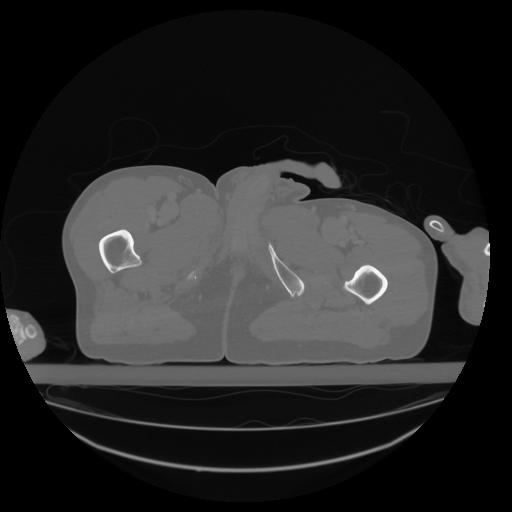

34 CUERPO,CE,Vol,1.0,CUERPO,,